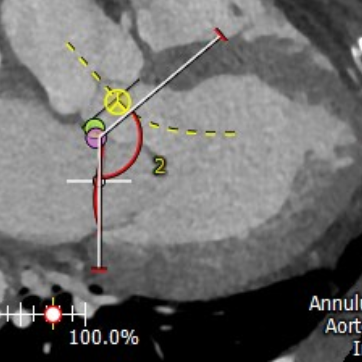

术前,武汉协和医院专家团队基于对患者详尽的CT测量分析,认为患者不适合外科开胸手术,故决定实施微创经导管二尖瓣植入。团队通过CT影像分析二尖瓣瓣环、测量其径线、计算二维投影径线并模拟植入TruDelta®经导管二尖瓣瓣膜系统,提前规划穿刺路径和人工瓣膜植入位置,降低手术风险。

CT评估:瓣环夹角